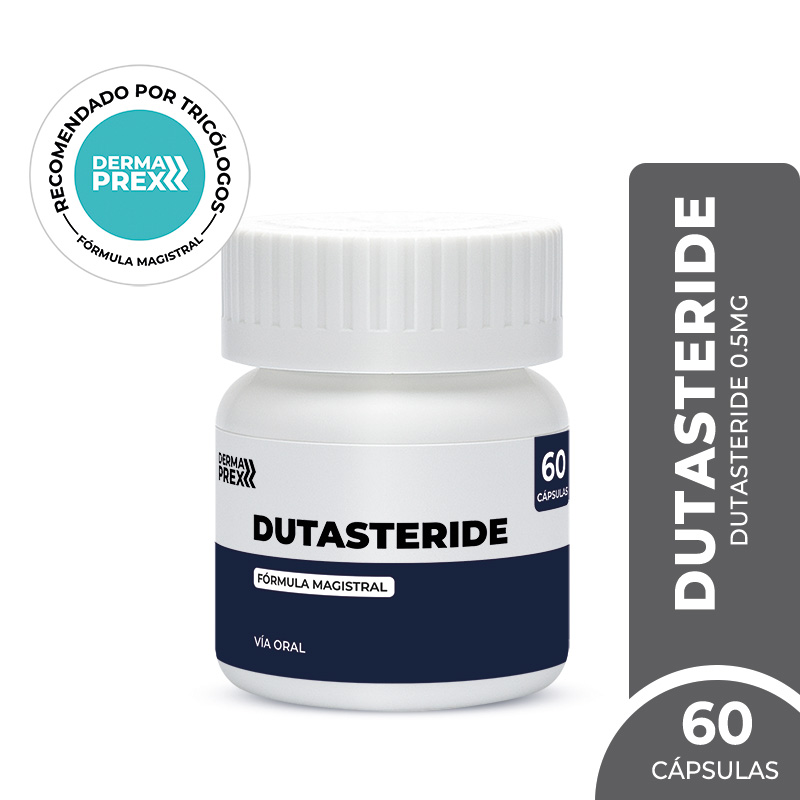

60 CÁPSULAS

Tratamiento capilar avanzado 60 cápsulas

30% OFF

Dermaprex

Usa el cupón

DERMANIGHT

al finalizar tu compra

Dermanight:

S/ 200.20

Ver producto